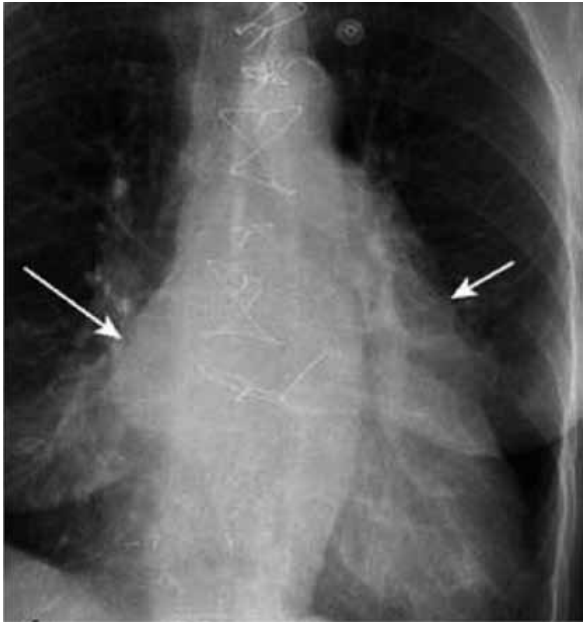

As setas na radiografia a seguir indicam a dilatação da(s) seguinte(s) câmara(s) cardíaca(s):